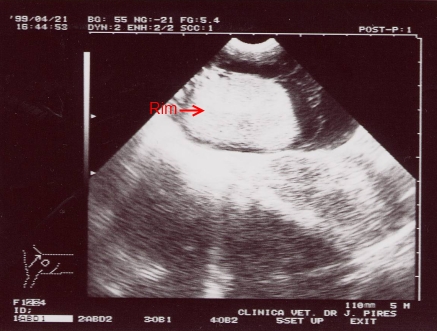

Ecografia: Rim dirtº, Cortex e medula hiperecogenicos envoltos por liquido hipoecogenico intracapsular.

A imagem é de um pseudo quisto perirrenal felino. Há acumulação de lÃquidos a envolver toda a cápsula mantendo intacta a estrutura renal. |

A imagem da Ecografia foi determinante. A renomegalia resultante da hemorragia intracapsular confirmou o diagnóstico de um Pseudoquisto Perirrenal Felino por causa traumática.